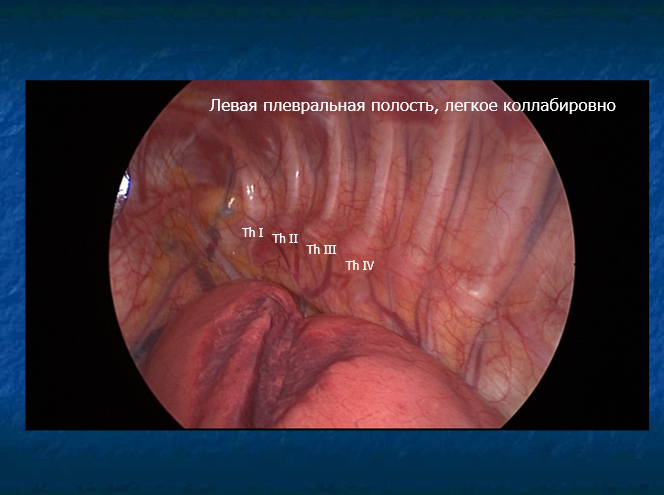

Суть операции заключается в торакоскопическом (через небольшие проколы) удалении симпатических нервных ганглиев с левой стороны. Эта процедура значительно снижает симпатические влияние на сердце. У девочки аритмии были стресс-индуцированными: любая физическая нагрузка или боль, несмотря на прием бета-блокаторов, приводила к учащенному сердцебиению. Симпатэктомия уменьшает симпатическую активность и контролирует тахиаритмию.

Зона операции. Место удаления симпатических ганглиев.